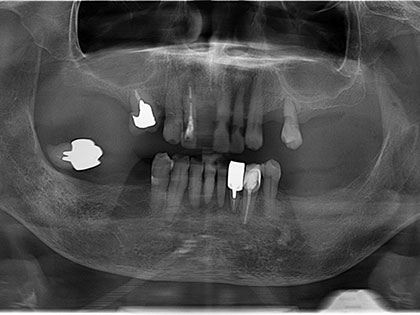

• 全体的に歯周病が進行しており、レントゲン写真をみますと青い線が根の先、赤い線が歯を支えている骨のある位置です。黄色の×は抜歯した歯です。

• 今までと同様なバネを残っている歯にかけると、残っている歯が更にグラグラして、最終的には自分の歯が痛みが強くなり抜歯になります。

• それであれば歯の神経を取り、その上にマグネット(磁石)を装着した方が根の寿命も延びますし、バネで揺れ動き入れ歯がすれて歯肉が痛くなることも少なくなります。

• 今回、極端に悪い歯は抜きました。

• 今回は上下に5か所ずつマグネットを装着し、その上に金属床義歯を上下にセットしました。